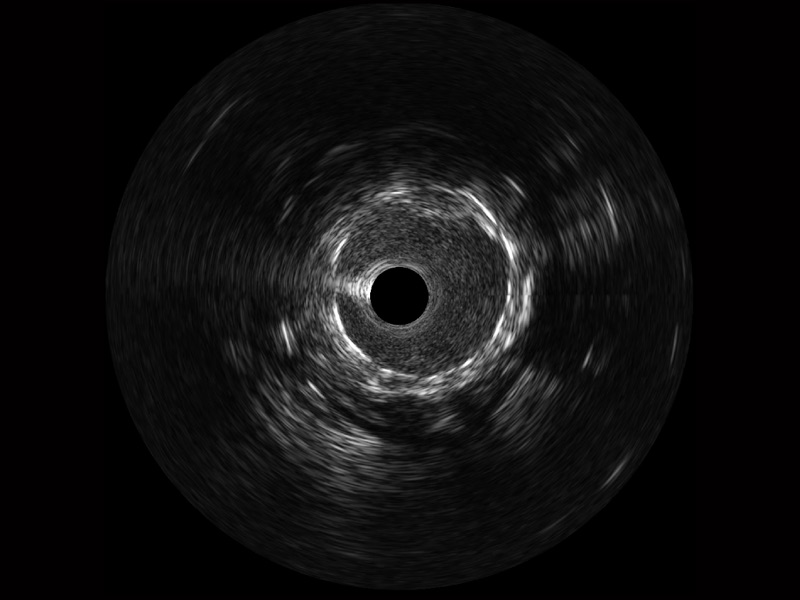

傳統(tǒng)IVUS圖像

對(duì)比傳統(tǒng)IVUS導(dǎo)管成像,開(kāi)立寬頻IVUS圖像的近場(chǎng)支架梁顯影更細(xì)膩,遠(yuǎn)場(chǎng)中膜外血管仍清晰可辨,兼顧遠(yuǎn)中近,兼顧分辨力與穿透深度